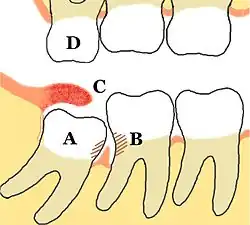

A = Retinierter Weisheitszahn 48 mit mesialer Karies;

B = distale Karies am Zahn 47, dazwischen Gingivitis;

C = entzündete, künstliche Zahnfleischtasche;

D = Elongierter Zahn 18

Ursache

Die Dentitio difficilis tritt als Dentitionsstörung im bleibenden Gebiss fast ausschließlich beim Durchbruch von Weisheitszähnen auf, vorwiegend im Unterkiefer. Die Ursache liegt im Platzmangel für diese (zuletzt durchbrechenden) Zähne. Der Platzmangel entstand in der menschlichen Evolution durch eine bei zahlreichen Menschen entstandene Verkürzung des Unterkieferkörpers. Im Unterkiefer kommt hinzu, dass durch den aufsteigenden Ast des Unterkiefers (Ramus mandibulae) an der distalen Fläche der Zahnkrone oft eine Zahnfleischtasche entsteht, die der Zahnreinigung nicht hinreichend zugänglich ist. In dieser künstlichen Zahnfleischtasche können sich Bakterien und Speisereste ansammeln, die zu einer eitrigen Entzündung führen. Besonders bei einem verlagerten oder teilretinierten Zahn ist diese Gefahr gegeben, wobei dann auch andere Zahnflächen als „Schmutzwinkel“ in Frage kommen. (Siehe nebenstehende Abbildung)